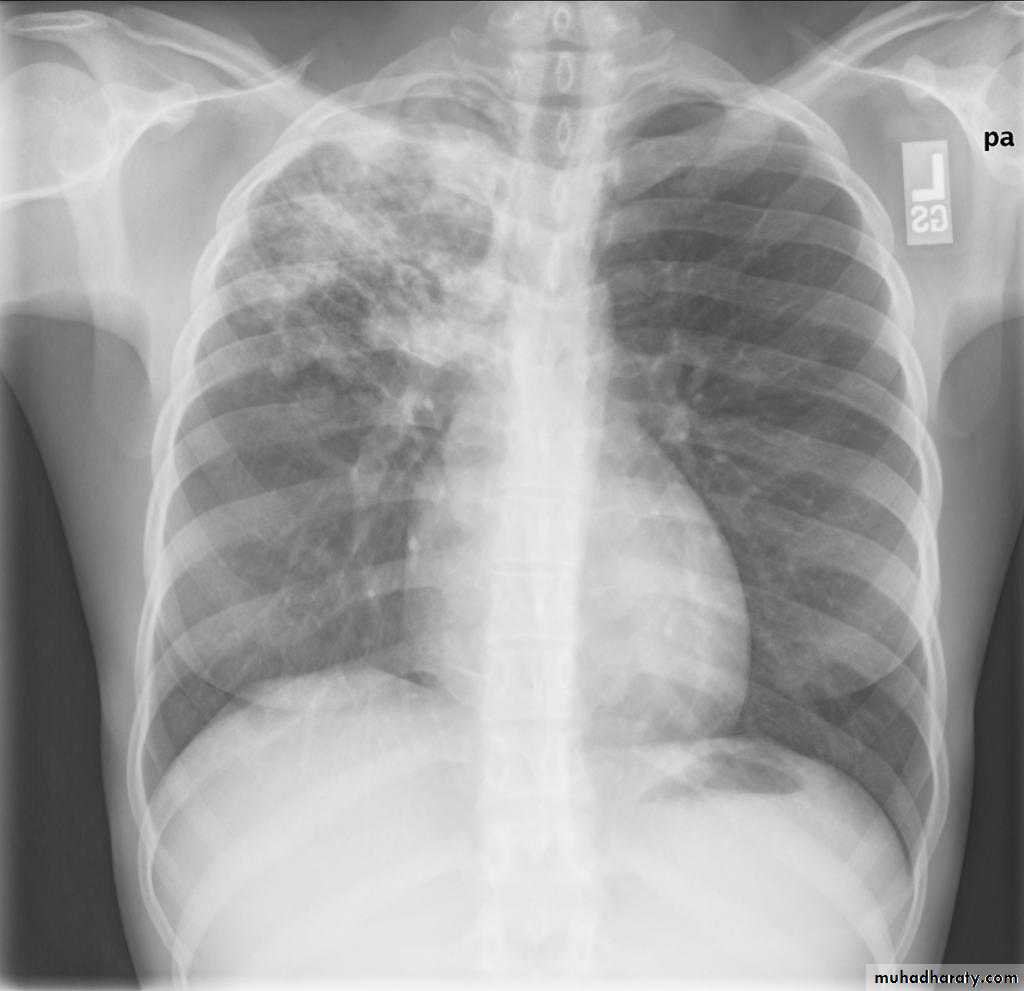

Radiographic featuresprimary pulmonary tuberculosis

1.the initial focus of infection can be located anywhere within the lung and has non-specific appearances ranging from too small to be detectable, to patchy areas or consolidation or even lobar consolidation in RT upper or RT middle lobe . Radiographic evidence of parenchymal infection is seen in 70% of children and 90% of adults called Ghon lesion , +/- ipsilateral hilar or paratracheal Lymph adenopathy usually right sided

( Ghon focus + LAP ) called primary complex.

2.Later In most cases, the infection becomes localized and a caseating granuloma resolve eventually calcifies with or without calcification of the regional LN , Calcification of nodes is seen in 35% of cases . When a calcified node and a calcified Ghon lesion are present, the combination is known as a Ranke complex.

3. Pleural effusions are more frequent in adults .